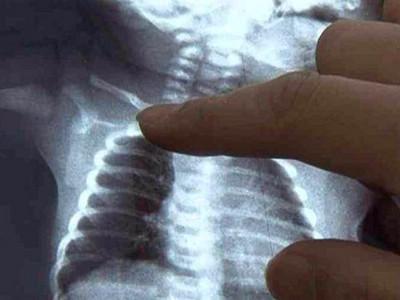

新生小孩锁骨骨折怎么办?新生儿锁骨骨折是新生儿娩出过程中最常的骨折。新生儿锁骨骨折治疗简易,预后良好,没有并发症,故不应采取任何过激的治疗方法新生婴儿的锁骨骨折,大多数是产伤,而且几乎都是顺产的,这种骨折比较常见。

有些出生后,家人并不知道锁骨发生骨折,只是骨折的这一边手臂活动比较少,引起雷注意,一拍片,才发现有骨折。有的是给孩子洗澡穿衣服的时候,孩子哭泣,另一边则没有这样的情况,引起家人都注意,才发现的。也有的家长比较细心,看见锁骨的地方两边不一样,一边明显鼓起来,摸或者按压会引起孩子哭闹挣扎,引起注意,去拍片才发现有骨折。

绝大多数新生儿锁骨骨折是不需要治疗的,只要这边的手臂穿衣服和洗澡的时候轻柔一些即可。也有的家长一直没发现,知道骨折愈合后,形成骨痂,那个地方鼓了起来,才发现,不过这个时候,孩子已经活动自如了。一般在10天左右,就会愈合,不需要任何治疗。虽然对位对线不好,愈合后有个鼓起来的包包,硬硬的,以后会慢慢塑形,包包会逐渐消失。所以是不需要担心的。